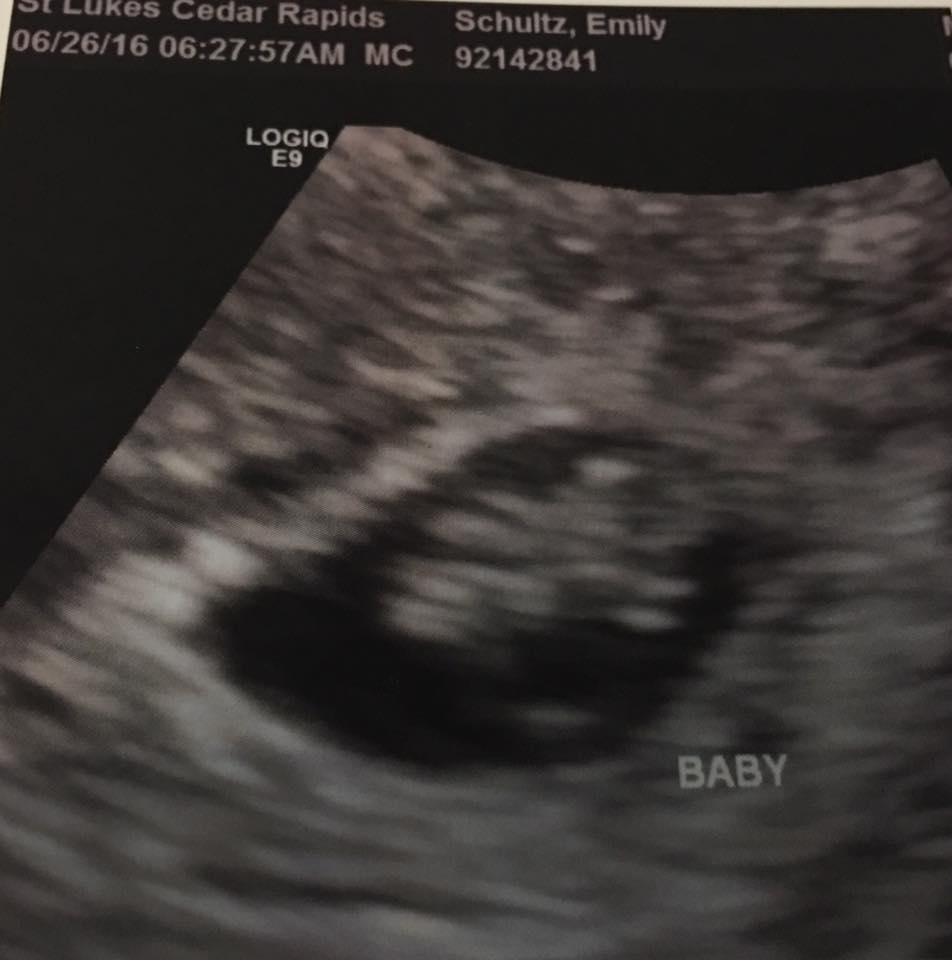

Anyone good at Ramzi method?? I have had four scans this pregnancy so far due to a SCH at 6, 7, 8, and today at 9+2. Just wondering your thoughts on this method, I know it's early and not 100% ;-)

Attachment 32033Attachment 32034Attachment 32035Attachment 32036